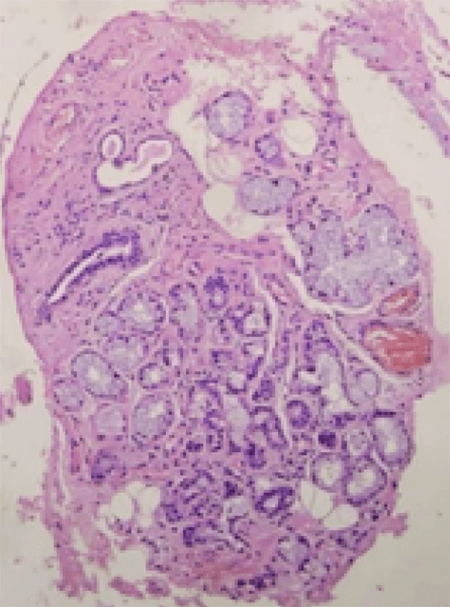

1. Epitelio plano estratificado con hiperplasia epitelial. El tejido conectivo muestra numerosas glándulas mucosas. H&E x40. Fig. 5.

2. Figura 5. Epitelio plano estratificado con hiperplasia epitelial. El tejido conectivo muestra numerosas glándulas mucosas. H&E x40.

3. Acinos mucosos y estructuras ductales. H&E x200. Fig. 6.

5. Acinos mucosos. Presencia de ectasia ductal. H&E x100. Fig. 7.

La existencia de un epitelio plano estratificado con hiperqueratinización, la hiperplasia adenomatoide, la atrofia acinar y la ectasia ductal, característi- cas encontradas en el paciente, son parámetros reconocidos como criterios histológicos para el diagnóstico de esta entidad2.